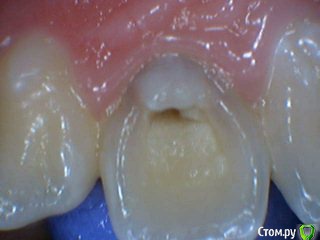

Давлетшин Опубликовано 13 июля, 2017 Поделиться Опубликовано 13 июля, 2017 Обидно понимаешь за детство, сообщений особо нет. подумать не над чем.два клинических случая. будут там пульпиты или нет? вот в чем вопрос. в одном случае пломба Витример в другом Эстелайт, без прокладок. Порядок фото несколько нарушен. Работаем над этим. Ссылка на комментарий

Mikhail_29_rus Опубликовано 17 июля, 2017 Поделиться Опубликовано 17 июля, 2017 Все будет хорошо , пульпит далеко Ссылка на комментарий

Dok22 Опубликовано 28 июля, 2017 Поделиться Опубликовано 28 июля, 2017 На всякий случай рентген контроль раз в пол года пару лет и проверка на витальность. Ссылка на комментарий